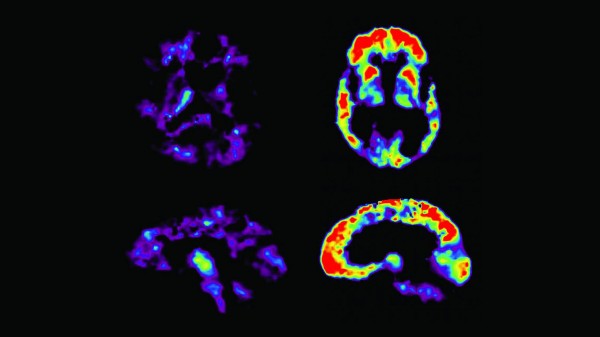

Usare Google, invece di cercare informazioni nel cervello, potrebbe metterci a rischio di demenza, ha avvertito un esperto.Il professor Frank Gunn-Moore, importante ricercatore di demenza, dice che la nostra dipendenza da Internet è un 'esperimento'...